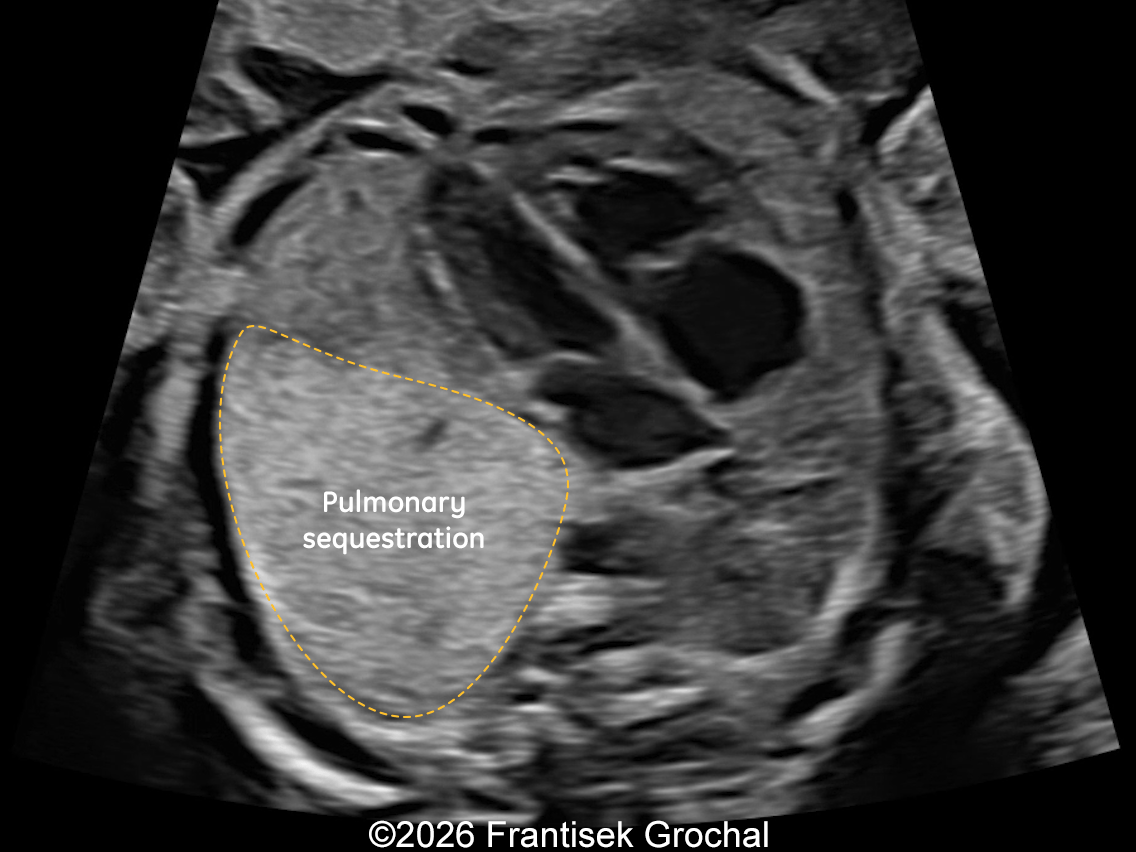

22+3 weeks of gestation – sagittal view demonstrating a well-circumscribed, triangular pulmonary sequestration.

Image 1 22+3 weeks of gestation – sagittal view demonstrating a well-circumscribed, triangular pulmonary sequestration.